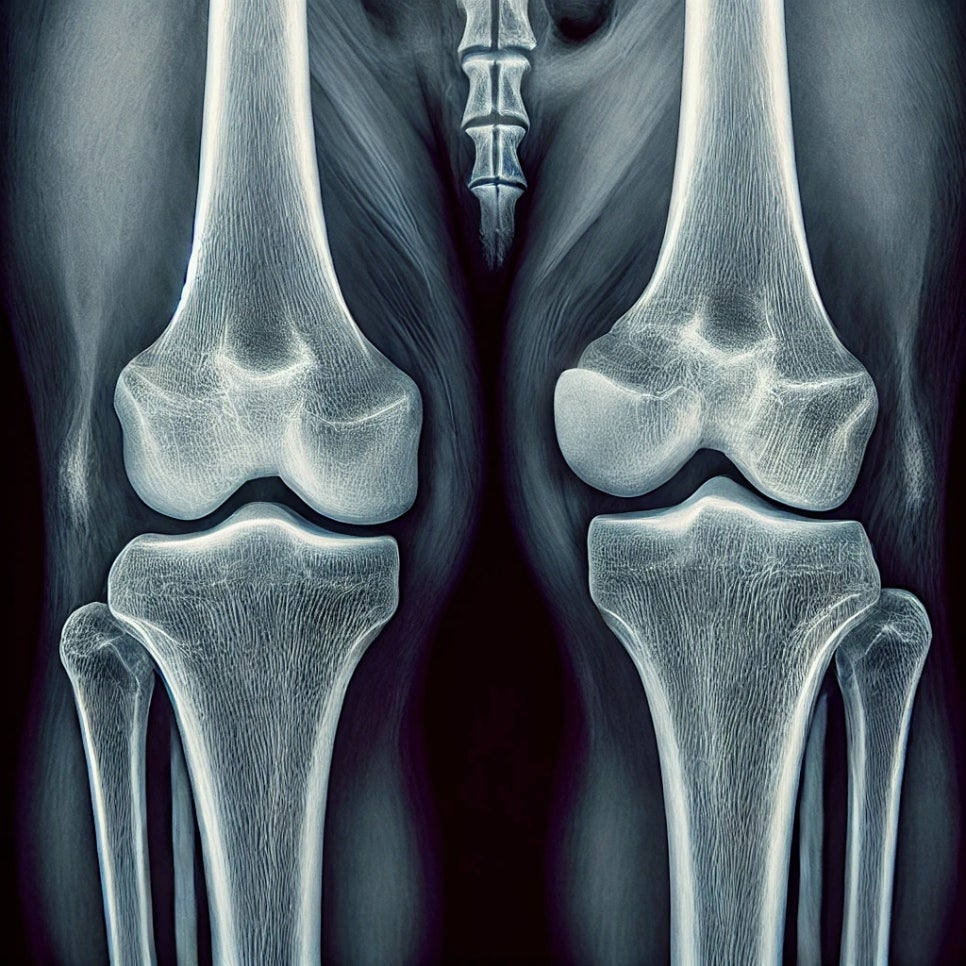

강아지 슬개골 탈구는 소형견에서 흔히 발생하는 질환으로, 무릎의 슬개골(무릎뼈)이 정상적인 위치에서 벗어나 탈구되는 것을 말합니다. 슬개골 탈구는 반려견의 활동성을 저하시키고, 적절한 치료가 이루어지지 않으면 만성적인 통증과 관절염으로 이어질 수 있습니다. 이번 포스팅에서는 강아지 슬개골 탈구 증상에 대해 알아보고, 그에 따른 대처 방법을 설명해 드리겠습니다.

가장 흔한 강아지 슬개골 탈구 증상 중 하나는 강아지가 뒷다리를 들고 걷거나 절뚝거리는 것입니다. 이는 슬개골이 정상 위치에서 벗어나 무릎이 불안정해지기 때문에 발생합니다. 탈구된 슬개골이 자연스럽게 제자리로 돌아오면 강아지는 다시 정상적으로 걷기 시작할 수 있지만, 반복적으로 이런 행동을 보인다면 슬개골 탈구를 의심해야 합니다.

강아지 슬개골 탈구 증상 중 통증을 동반하는 경우가 있습니다. 강아지의 무릎 부위를 만졌을 때 강아지가 갑자기 움찔하거나 통증을 호소하는 반응을 보인다면 슬개골 탈구를 의심해볼 수 있습니다. 이러한 통증은 특히 탈구가 진행될수록 심해지며, 강아지가 무릎을 만지지 못하게 하는 경우도 있습니다.